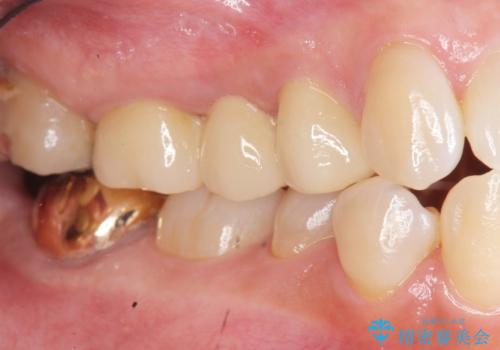

- 33万円(仮歯・ジルコニアクラウン×3)費用は治療当時の料金となります

ブリッジは隣の歯を削り、クラウンにしなければならないというデメリットはありますがインプラントと異なり手術をしなくてもよく、入れ歯よりも一般的にしっかりと噛むことができます。